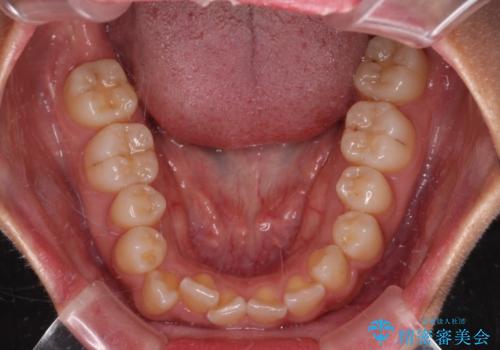

デコボコと捻れて前に飛び出した歯列 抜歯矯正でスッキリした口元に

- 前歯のデコボコと口元の突出感を気にして来院された患者様です。

非抜歯矯正ではデコボコを解消することでより口元が突出してしまうため、上下左右の小臼歯4本の抜歯を行い、ワイヤー装置による矯正治療を行うこととしました。